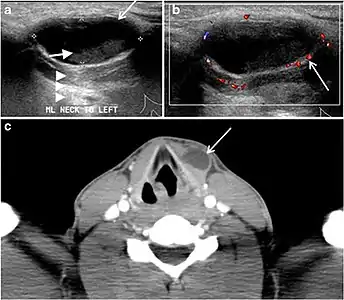

Ectopic thyroid tissue may be detected in the tongue near the foramen cecum (90%) and along the midline between the thyroid isthmus and posterior tongue, lateral neck, mediastinum, and oral cavity. The most frequent location is the base of the tongue (Figs. 16, 1717 and and18).18). In 70% of cases, the ectopic thyroid is the only functional thyroid tissue present in the body (Fig. 18).[1]

Ectopic thyroid tissue lateral to the orthotopic midline location is rare. The exact anatomical definition of this rare entity is debated in the literature. To avoid confusion, some authors define a lateral neck ectopic thyroid as any thyroid tissue superficial to the strap muscles with no midline continuity. The majority of lateral thyroid ectopia cases have been reported as lesions closely related to the strap muscles. There are few reported cases of ectopic lateral thyroid tissue in the submandibular region, jugulodigastric region, or within the parotid gland substance (Fig. 17).[1]

A thyroglossal duct cyst (TDC) is a duct remnant between the foramen cecum and thyroid isthmus. Most TDCs are located below the hyoid bone and in the midline. The more caudal the cyst, the more likely it will be off midline within 2 cm (Fig. 19 and and20).20). On a CT scan, a TDC appears as a well-circumscribed area of fluid attenuation with thin walls. The cyst wall can become thick with an enhancing rim indicative of current or previous infection. These cysts maybe complicated by haemorrhage, infection, or malignancy. Therefore, their US and CT scan appearance may vary based on their content. Nodular enhancement within a TDC should initiate further workup to exclude malignancy (Fig. 21). US-guided FNA of these suspicious nodular areas is considered an appropriate next diagnostic step, taking into consideration the high rate of false negative results.[1]